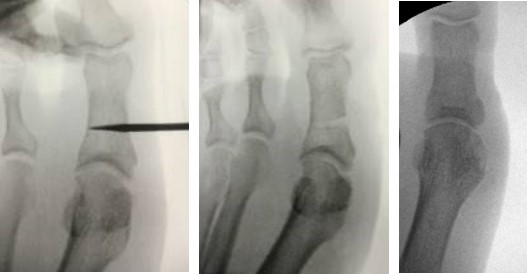

Die Akin-Osteotomie erfolgt in mindestens 50% begleitend zu metatarsalen Osteotomien im Rahmen der Korrektur einer Hallux valgus Deformität 12. Diese gehören zu den am häufigsten durchgeführten orthopädischen Eingriffen. Eine präzise Planung der notwendigen Korrektur unter Berücksichtigung aller Komponenten ist daher unabkömmlich. Dabei sollte eine Valgus-Deformität der Grundphalanx mitbehandelt werden, da diese die Entwicklung eines Rezidivs begünstigt. Die valgische Deformität der Grundphalanx mit veränderten Gelenksflächenwinkeln wird als Hallux valgus interphalangeus bezeichnet (Abb. 1). Dabei können verschiedene Winkel zur Definition der Fehlstellung angegeben werden (Abb. 2) 34. Bei der Beurteilung des Hallux valgus interphalangeus im Rahmen einer Hallux valgus Deformität ist zu beachten, daß häufig eine Hyperpronation der Grundphalanx besteht. Durch diese Malrotation werden die eigentlichen pathoanatomischen Winkel "verprojiziert". Am Röntgenbild erscheinen diese projizierten kleiner als die reellen Winkel. Somit sollte intraoperativ nach einer metatarsalen Osteotomie überprüft werden, ob eine Restfehlstellung im Sinne eines Hallus valgus interphalangeus besteht, da das präoperative Röntgenbild die Fehlstellung nicht immer exakt abbildet.

• Hallux valgus interphalangeus (Abb.1, Abb.2, Abb.3).

• Röntgenaufnahme des Fußes (unter Belastung) in dorsoplantarem und seitlichen Strahlengang (Abb. 3) und präoperative Fotodokumentation.

• Beurteilung des proximalen Gelenkflächenwinkels der Grundphalanx (Proximal Phalangeal Articular Angle, PPAA) des Hallux valgus interphalangeuswinkels (Hallux interphalangeus Angle, HIA) sowie des proximalen zum distalen Gelenksflächenwinkel (Proximal to Distal Phalangeal Articular Angle, PDPAA) 6789 (Abb. 2).

• Bildverstärker.